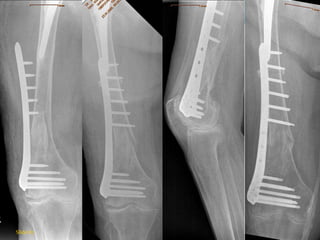

If bone is very poor, consider

Slide 93

TAKE-HOME MESSAGES

 Age & bone quality affect cortical and trabecular bone

in different ways

 Absolute stability often not possible

 Principles of fixation:

 Angular stability

 Fracture reduction

 Long bridging plates

 Enlarged surface area of implant / bone

 Augmentation

 Prosthetic replacement